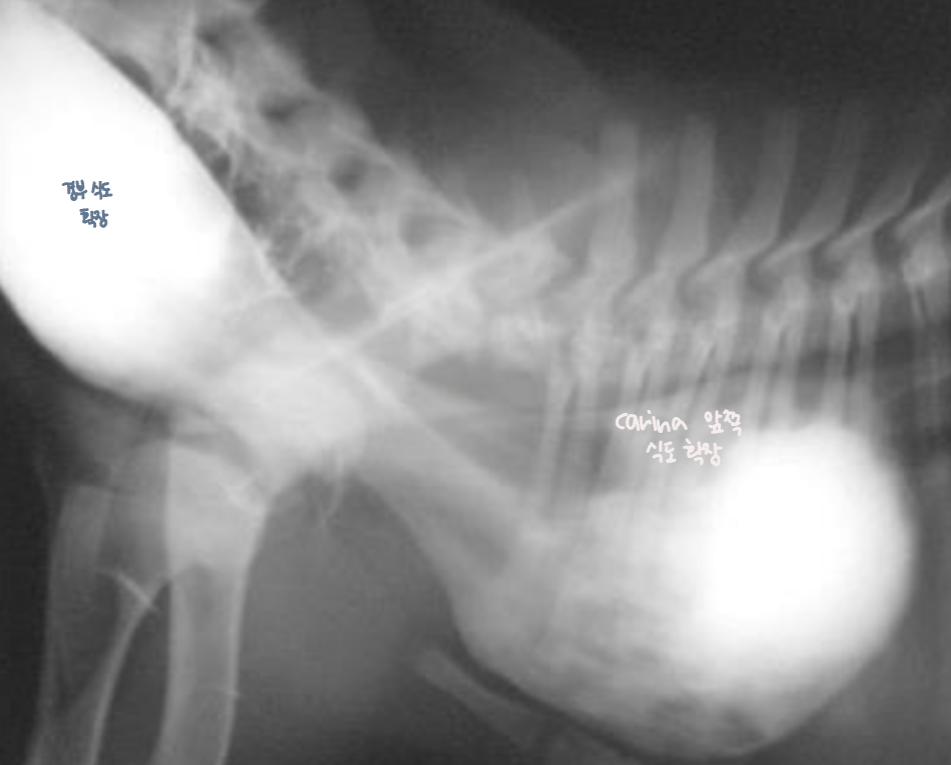

| PRAA์ ์ํ ์๋ํ์ฅ |

| - PRAA : VRA (Vascular ring anomaly)์ ํ ํํ. ์ ์์ ์ผ๋ก ํดํํด์ผ ํ ์ค๋ฅธ์ชฝ ๋๋๋งฅ๊ถ์ด ๋จ์์์ - 3rd right subclavian artery์ ์์กด : carina ์์ชฝ์ ์์นํ ๋๋๋งฅ๊ณผ ํ๋๋งฅ์ ์ฐ๊ฒฐ ๋ (ligamentum arteriosum)๊ฐ ์ ์์ ์ผ๋ก ํดํ๋์ง ์๊ณ band ๋ชจ์์ผ๋ก ์ ์ง๋จ โ carina ์์ชฝ์์ ์๋ ํ์ฅ โ ์ด๋ฆฐ ๋์ด์ regurgitation์ ๋ณด์ |